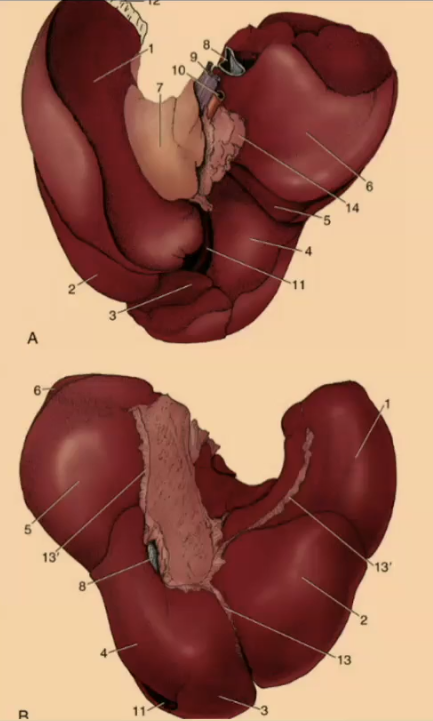

How many lobes are there to the liver?

4

What are the 4 lobes of the liver?

Left, Quadrate, Right, Caudate

#2?

Medial

#1?

Lateral

#3?

Quadrate

#4?

Medial

#5

Lateral

#6 & #7

Caudate